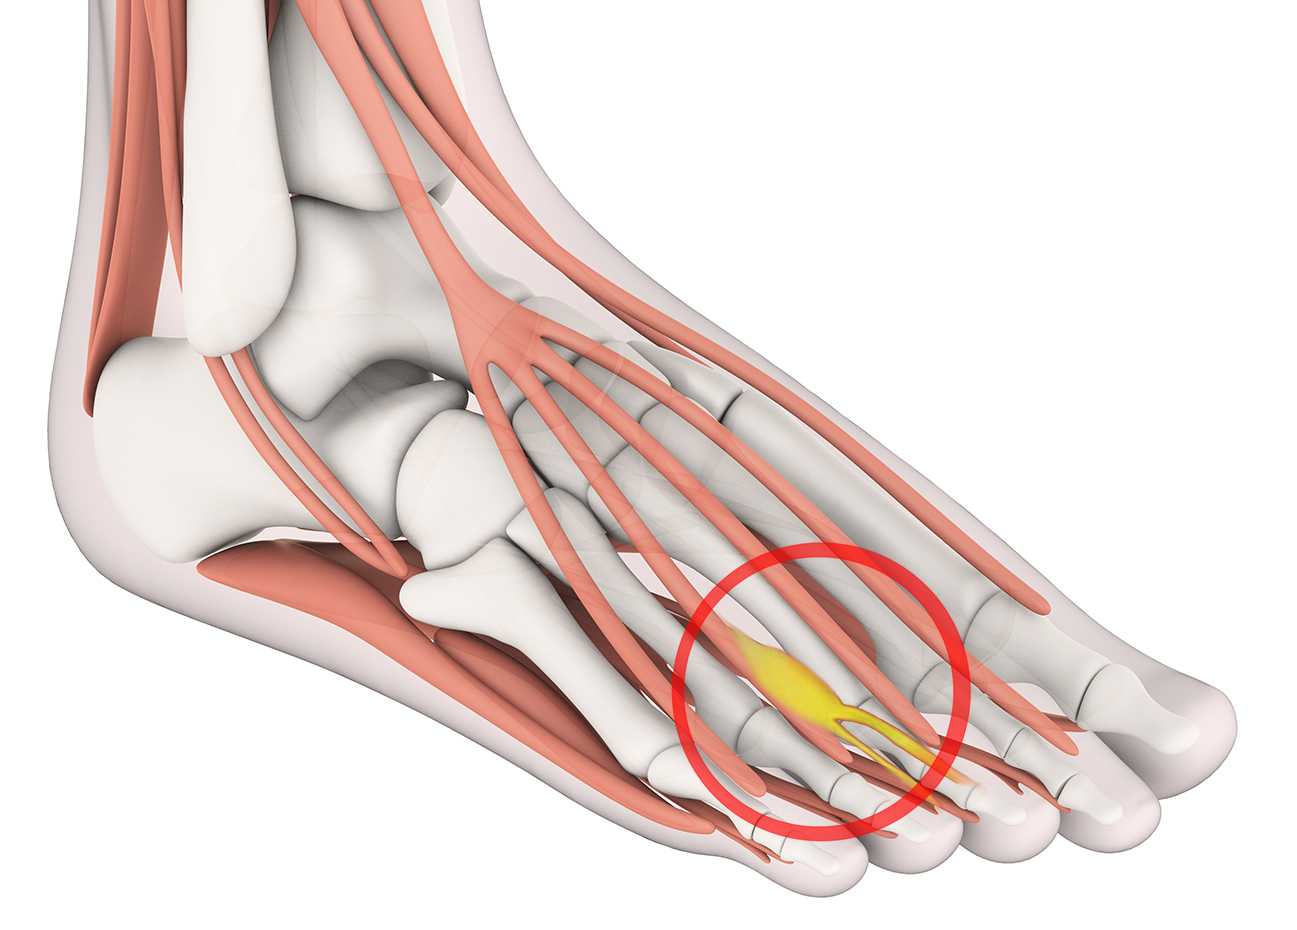

Разрастание нервной ткани, расположенной на подошве ноги, между 3-и и 4-м пальцами, называется невромой Мортона. Что это такое? Это фиброзное доброкачественное новообразование обычно поражает одну ногу, редко – обе сразу.

Заболевание проявляется в виде утолщения нерва на подошве, это сопровождается сильными болями, резко ограничивает человека в передвижениях. Когда у врачей появляется подозрение на развитие метатарзалгии Мортона, это говорит об опухолевом новообразовании нервной ткани, вызывающем сильные боли в плюсневых сочленениях.

По анатомии на этом участке стопы нерв делится на ветви, направляющиеся к боковым поверхностям пальцев, боль расходится именно в этих направлениях. По отзывам пациентов, столкнувшихся с невромой Мортона, они уже знают, что это такое и как лечить патологию, чтобы не довести болезнь до операции.